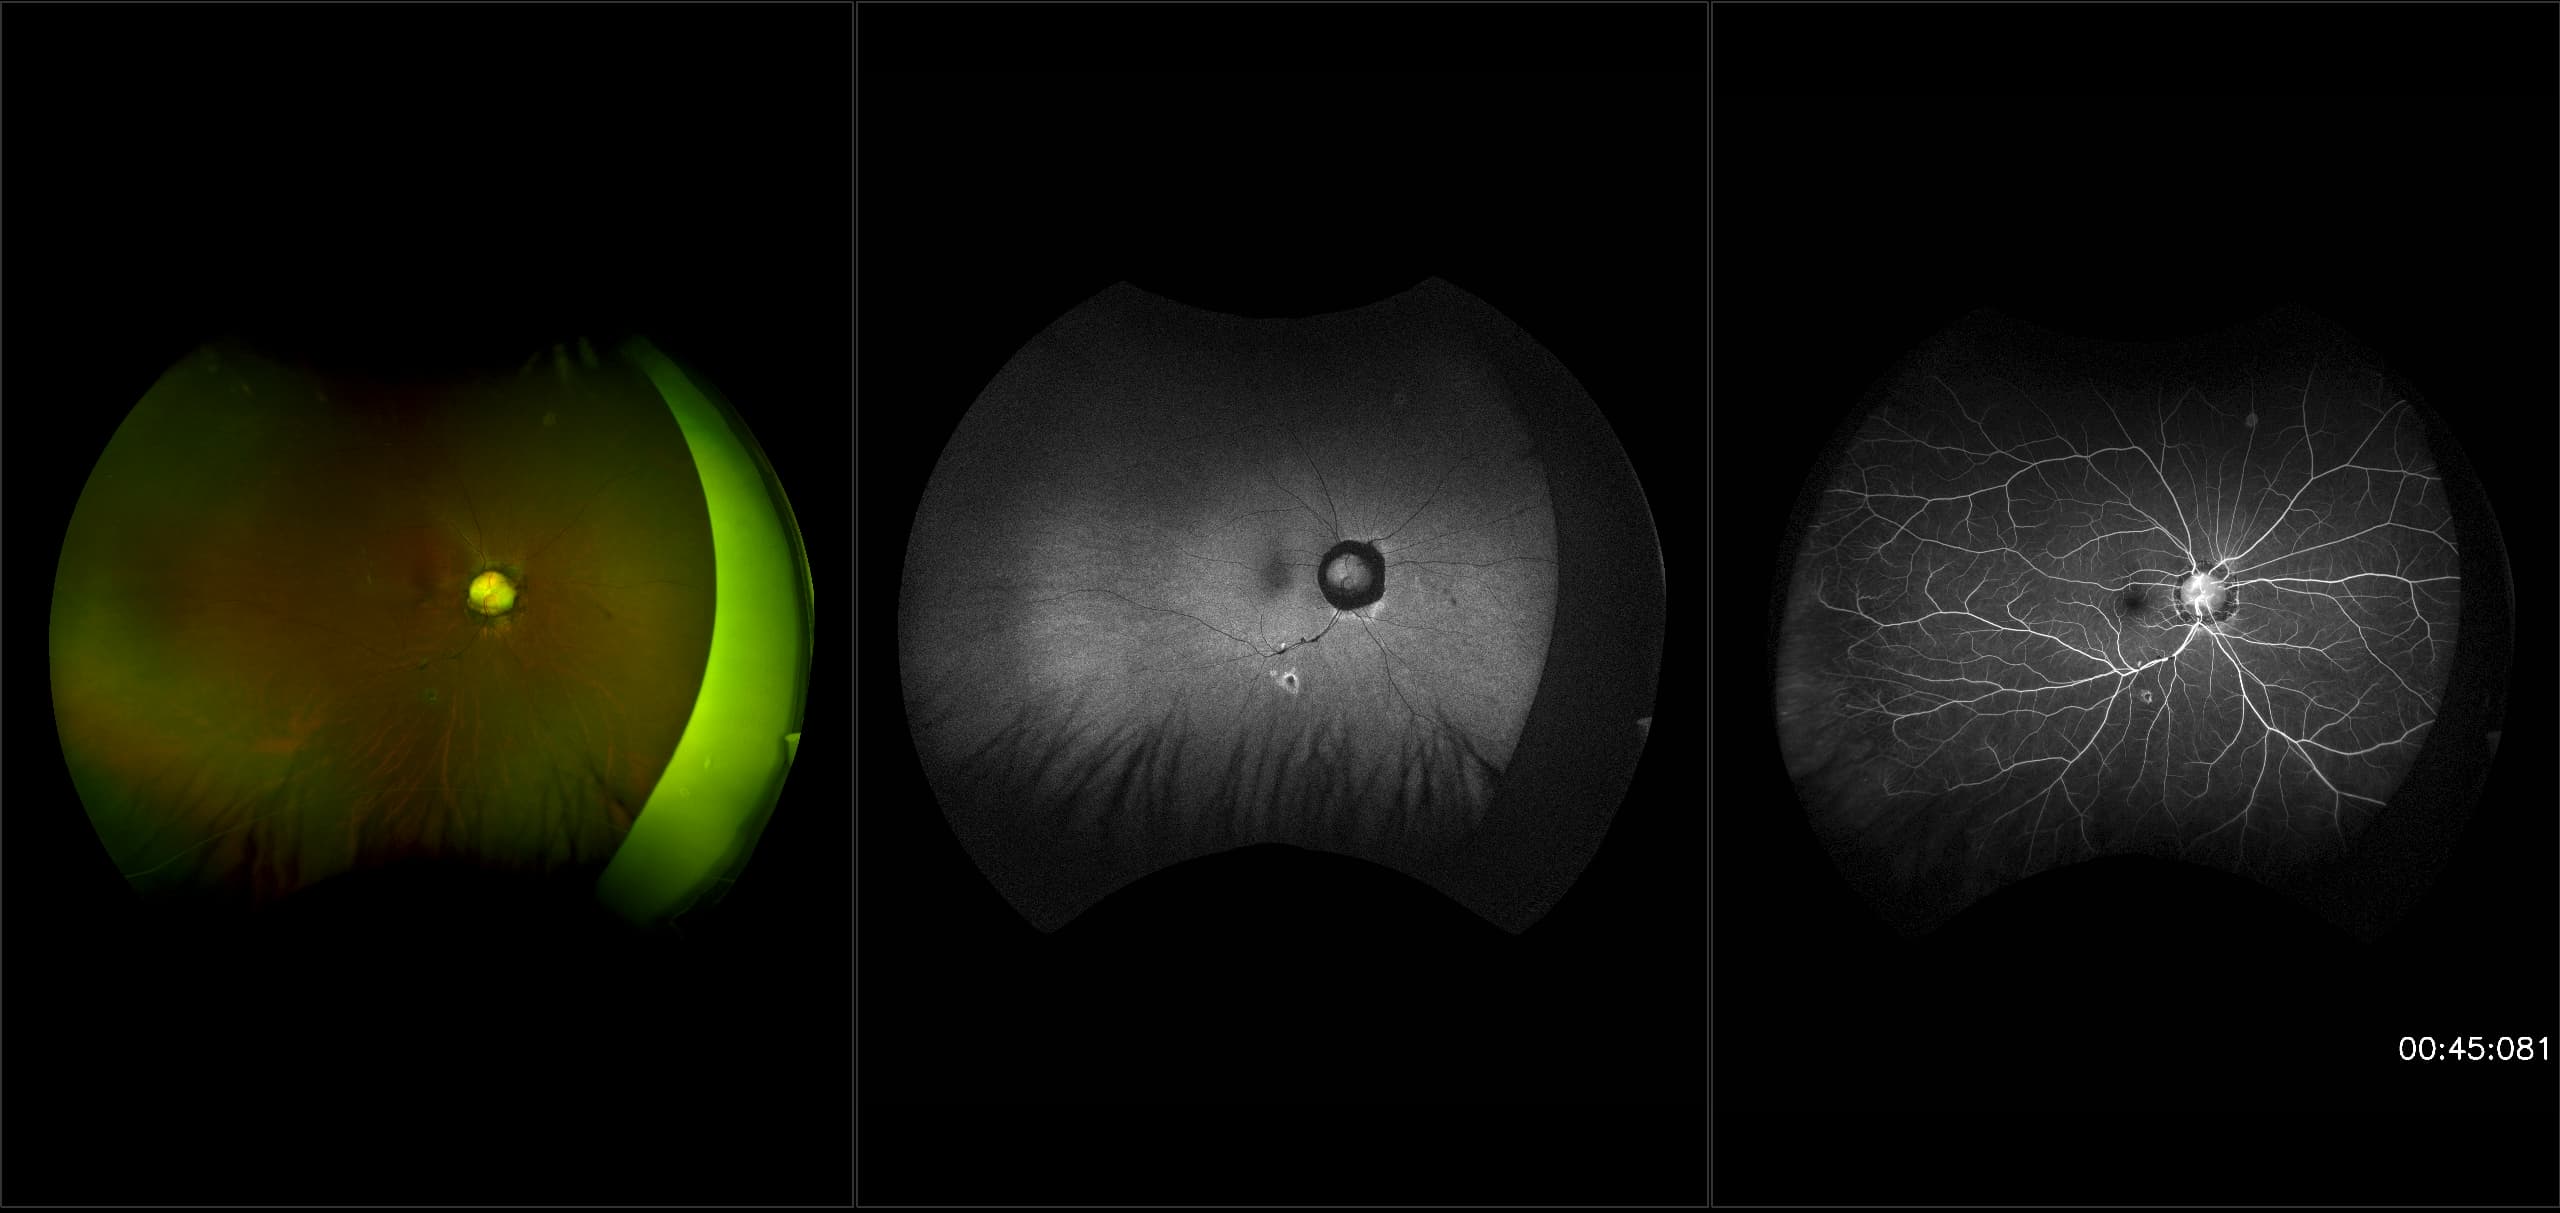

California - Large Pars Plana Cysts - Steered, RG

Pars plana cysts are a common peripheral retinal pathology that do not raise much clinical concern. They do not affect the central vision and observation alone is typically recommended. Pars plana cysts are something to be considered when peripheral retinal elevation is noted on routine exam.